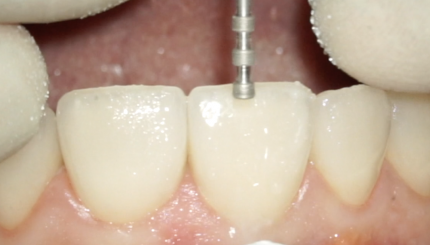

11 ЗАМЕНА СОБСТВЕННОЙ КОРОНКИ НА РЕФРАКТОРЕ